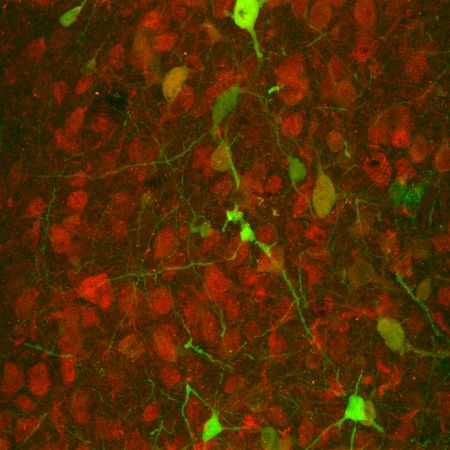

Applying optogenetics, the researchers used cone opsins from the mouse and human eye to control specifically serotonin signaling pathways either with blue or red light. The light-activated serotonin receptors can be switched on within milliseconds, are extremely light-sensitive in comparison to other optogenetic tools, and can be repetitively activated. "We hope that with the help of these optogenetic tools, we will be able to gain a better understanding about how anxiety and depression originate," states Dr. Olivia Masseck, a neuroscientist at Ruhr University Bochum.

The scientists also demonstrated that they were able to modulate mouse emotional behavior using the light-activated receptors. When they switched on the serotonergic signals by light in a certain brain area, the mice became less anxious.